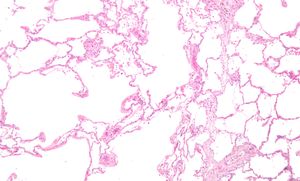

صورة مجهرية تظهر نفاخ الرئة (على اليسار - مساحات فارغة كبيرة) ونسيج الرئة مع محافظة نسبية على الحويصلات الهوائية (على اليمين).